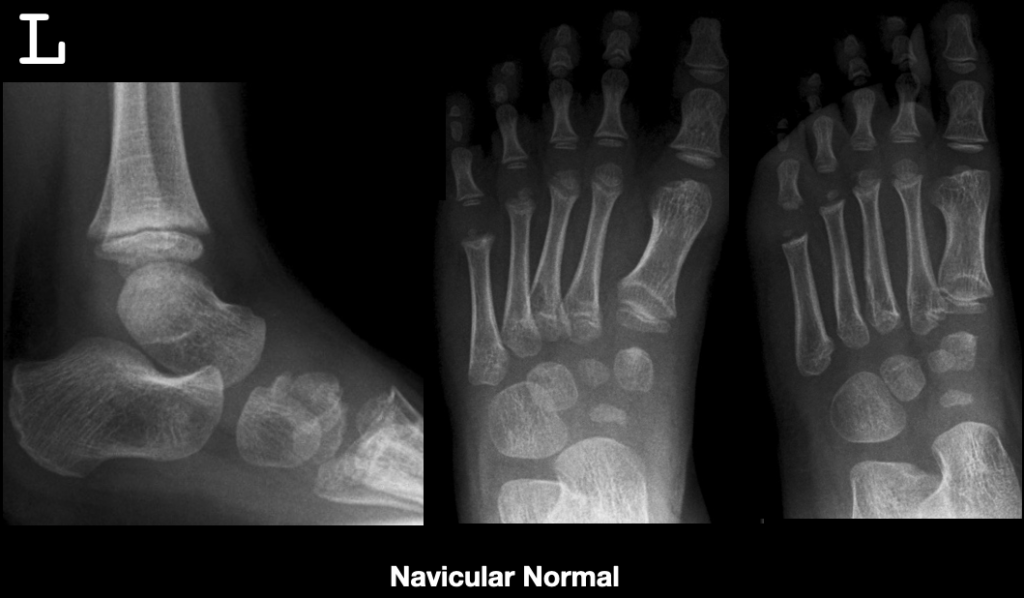

Figure 1 from Review Understanding Radiographic Changes Associated